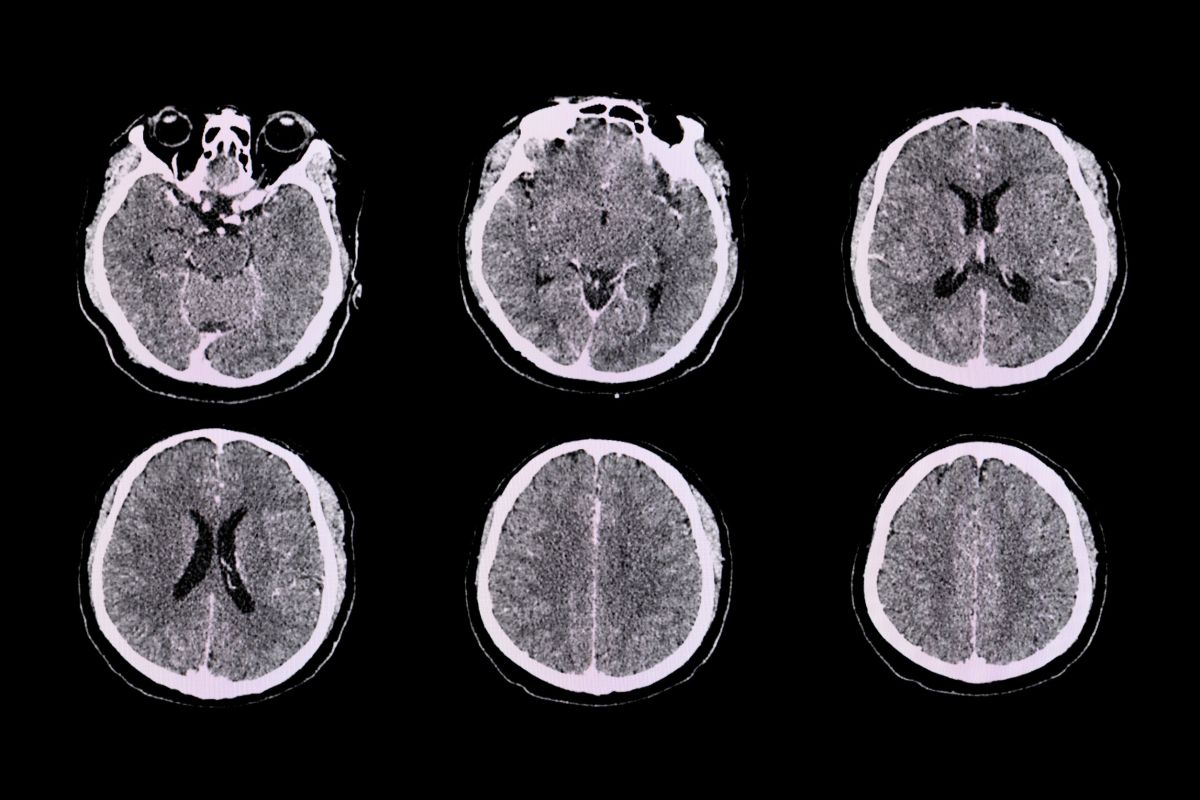

Con motivo de la celebración este domingo del Día Mundial de la Encefalitis, la coordinadora del Grupo de Estudio de Neurología Crítica e Intensivista de la SEN, la doctora Saima Bashir, explicó que “se llama encefalitis a la inflamación del cerebro que puede ser causada por una infección (encefalitis infecciosa) o por una reacción errónea del sistema inmunitario (encefalitis postinfecciosa o autoinmune)”.

Además, añadió, “también puede afectar a estructuras próximas del encéfalo, como las meninges (meningoencefalitis) o la médula espinal (mielitis o encefalomielitis). Debido a esta inflamación se producen cambios en el estado neurológico del paciente”.